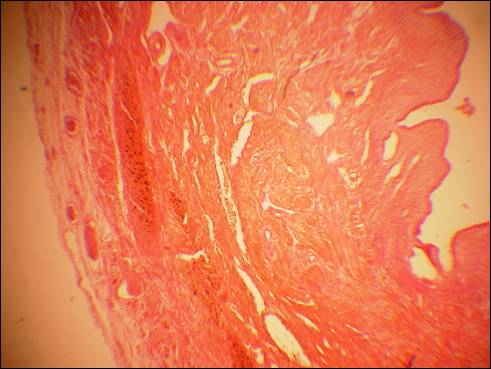

Нами предпринята попытка на светооптическом уровне оценить первые сроки появления лимфоидной ткани в составе структурных элементов органов женской репродуктивной системы. Было обнаружено, что первые структурно организованные и типичные лимфоидные узелки появляются в наружной оболочке влагалища плода на 22 неделе внутриутробного развития (рис. 1). Существенных различий в сроках и динамике развития лимфоидной ткани в органах репродуктивной системы плодов, развивающихся в условиях отягощённой и не отягощённой беременности, нам установить не удалось.

Рис. 1. Микрофото влагалища плода 22 недель (случай № 4). Поперечный срез в области середины влагалища. Лимфоидная ткань в виде узелков (а) в адвентициальной оболочке. Окр. гематоксилин-эозин, ув. х100.